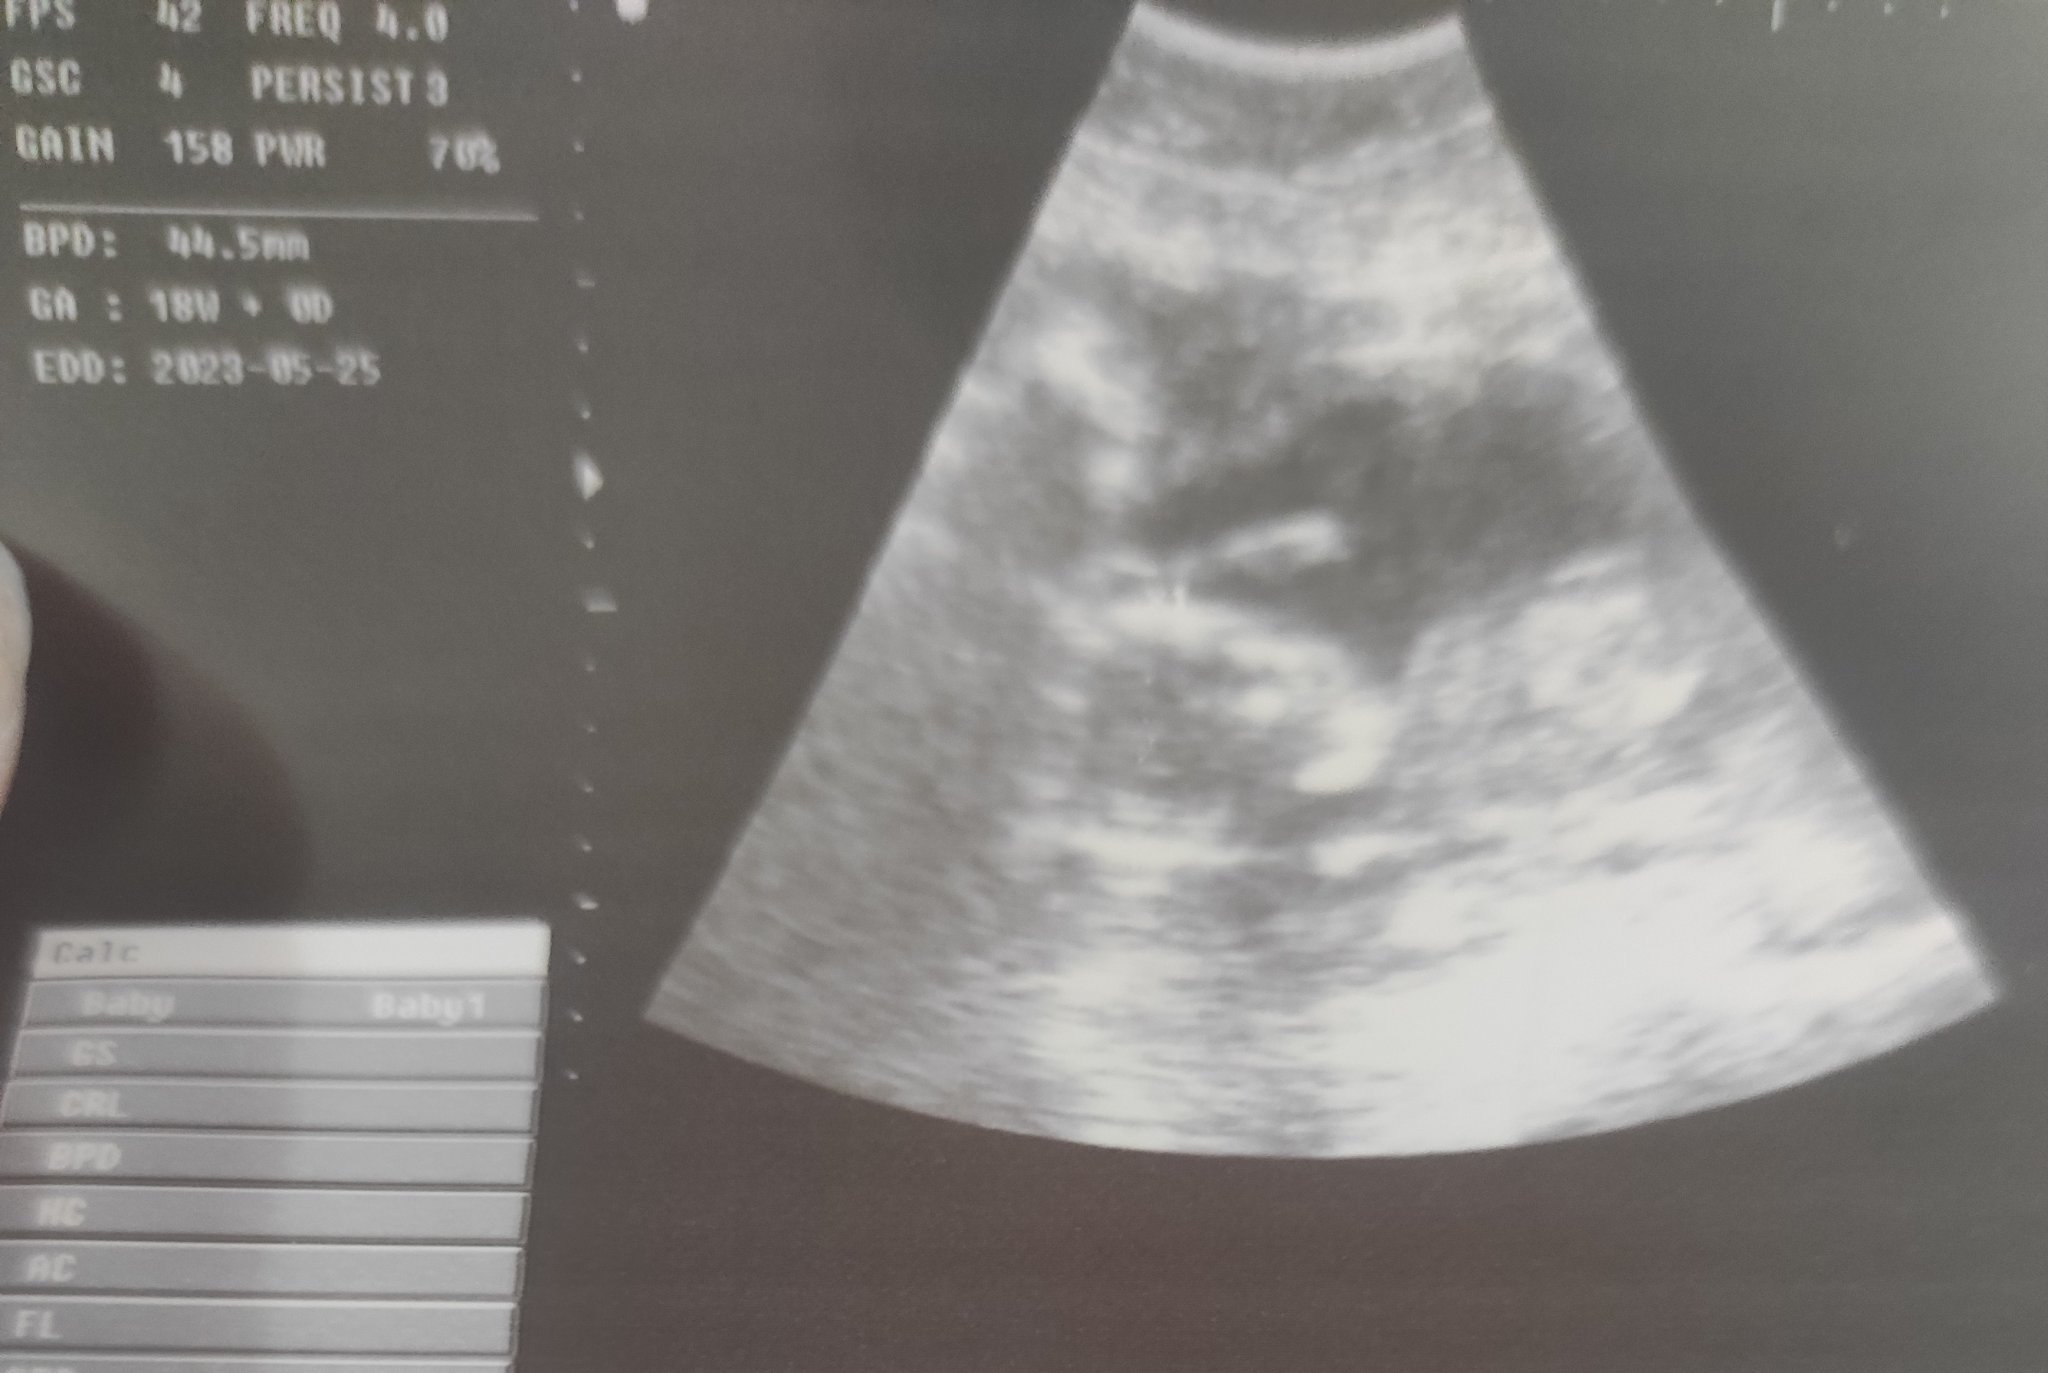

Какво представлява изображението от ехографията на 5-седмична и 2-дневна бременност?